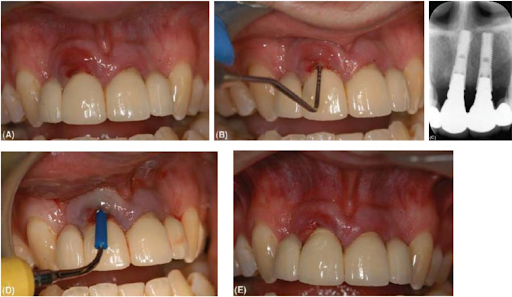

(A) Tình trạng viêm mô mềm xung quanh implant tại vùng răng cửa trên bên phải. (B) Ghi nhận độ sâu túi tại điểm giữa mặt ngoài là 6 mm. (C) Phim quanh chóp cầu răng cho thấy có sự tiêu xương (khoảng 2 mm) xung quanh implant bên phải. Vị trí chóp implant và abutment dài là lý do tại sao độ sâu túi đo được khá nhiều. (D) Sử dụng cây cạo vôi siêu âm với đầu nhựa lấy sạch mảng bám xung quanh bề mặt abutment. (E) Hai tuần sau khi loại bỏ mảng bám mô mềm đã có sự cải thiện nhưng vẫn cần phải tiến hành điều trị thêm nữa.

Thăm khám nha chu đạt chuẩn là sử dụng đầu thăm khám có đường kính khoảng 0.5 mm và lực thăm khám là 25g. Chiều sâu thăm khám lý tưởng phải tương đối (nhỏ hơn 4mm) không có hoặc rất ít chảy máu. Các nghiên cứu đã chỉ ra rằng việc thăm khám xung quanh implant không giống như thăm khám nướu tự nhiên. Một cách tổng quát, biểu mô bám dính khá mỏng manh và có thể bị chọc thủng bởi đầu thám trâm. Mô liên kết bên dưới quanh implant không được kết nối bởi các bó sợi chặt chẽ với abutment/bề mặt implant và các bó sợi collagen song song. Điều này dẫn tới sự đề kháng yếu với đầu thám trâm. Nên thăm khám phải trên mức xương 1mm. Nếu tăng thêm chiều dài thám trâm sẽ thấy sự gia tăng túi nướu, mô mềm chảy máu nhiều tiết dịch hay kém săn chắc đối với áp lực khám. Vùng thăm khám nên được kiểm tra bằng phim (không cần biết chụp phim có nằm trong kế hoạch hay không) để xác định liệu có tiêu xương viền hay là mất tích hợp xương.

Trong những trường hợp như vậy chúng ta nên tháo bỏ cấu trúc trên implant lưu giữ bằng vít để đánh giá riêng từng abutment và implant được chính xác hơn. Viêm mô mềm quanh implant có thể hồi phục nhờ việc chú ý vệ sinh răng miệng và làm sạch nhờ chuyên viên. Làm sạch nhờ chuyên viên nếu phục hình có thể tháo rời và làm sạch ngoài miệng. Tuy nhiên có phần lớn trường hợp đòi hỏi phẫu thuật nếu mô mềm gặp phải những vấn đề sau: